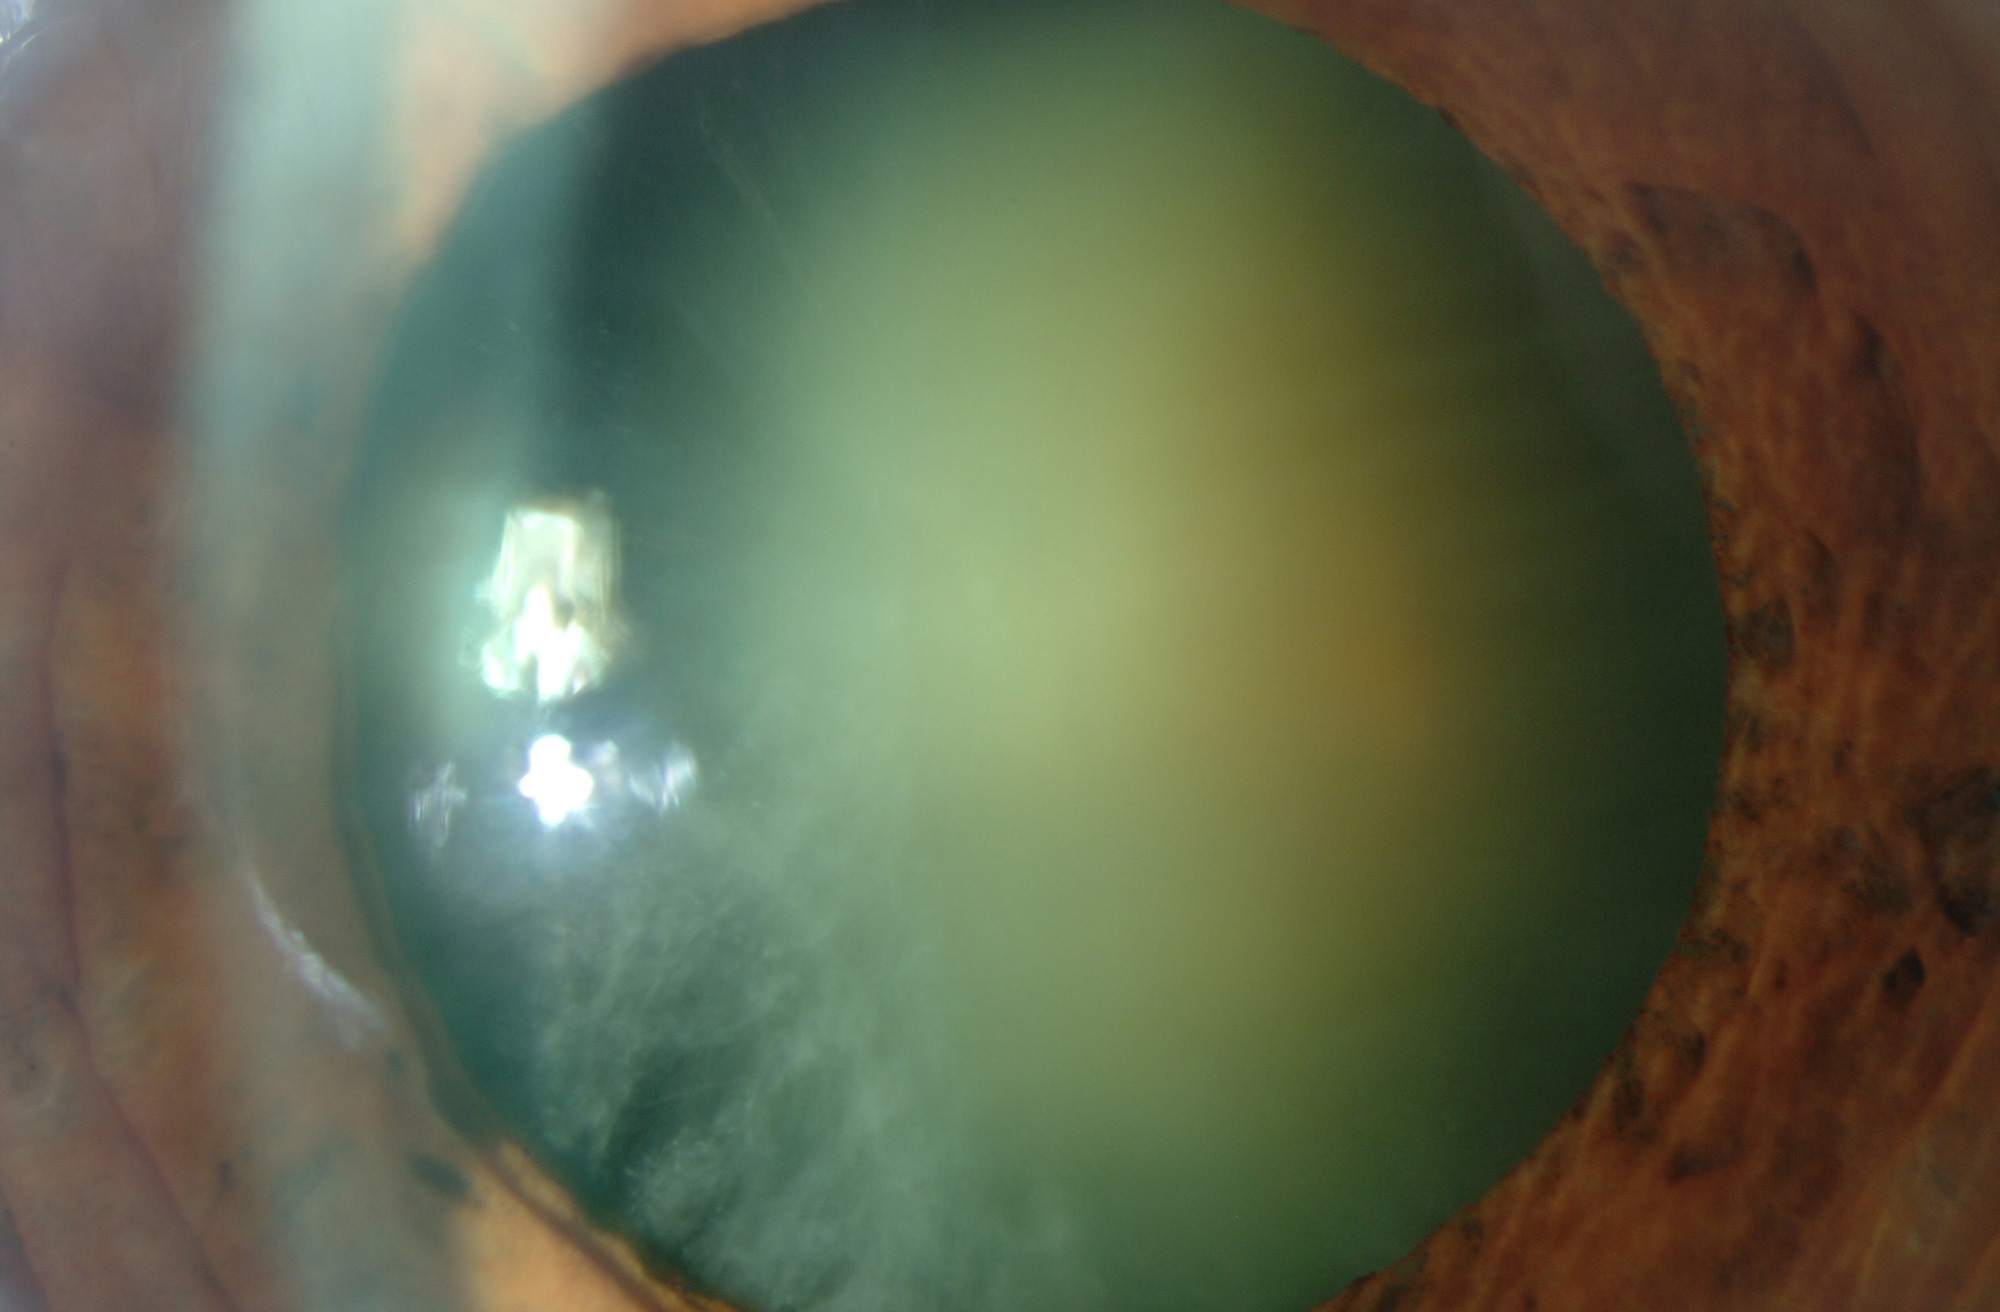

Catarata

La catarata es la opacidad parcial o total del cristalino que tiene lugar con el envejecimiento.